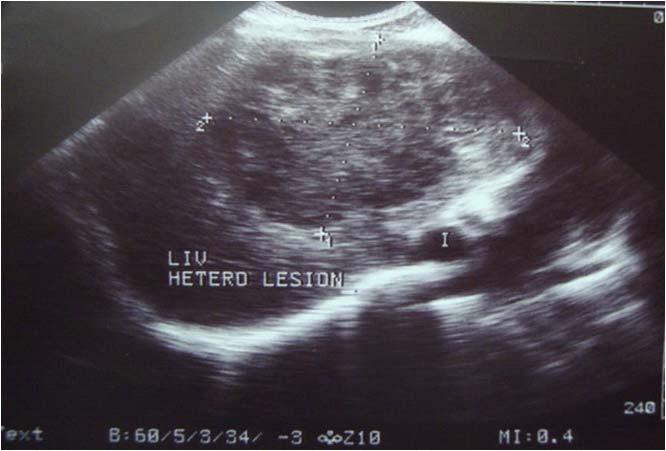

Radiological imaging was done in all the cases. USG findings revealed solitary masses in 45 cases (80.35%) and diffuse masses in 11 (19.64%). Solitary masses were around 45 in number out of which 30 were diagnosed as HCC. Right lobe had around 30 (66.7%) whereas left lobe had 15 (33.33%) masses respectively. Maximum (SOL’s) observed showed hyper-echogenicity present in 43 cases (76.78%). Heterogenous echotexture was observed in 6 cases (10.71%) (Fig 1).

Fig 1 — USG liver showing well defined heteroechoic lesion in left lobe